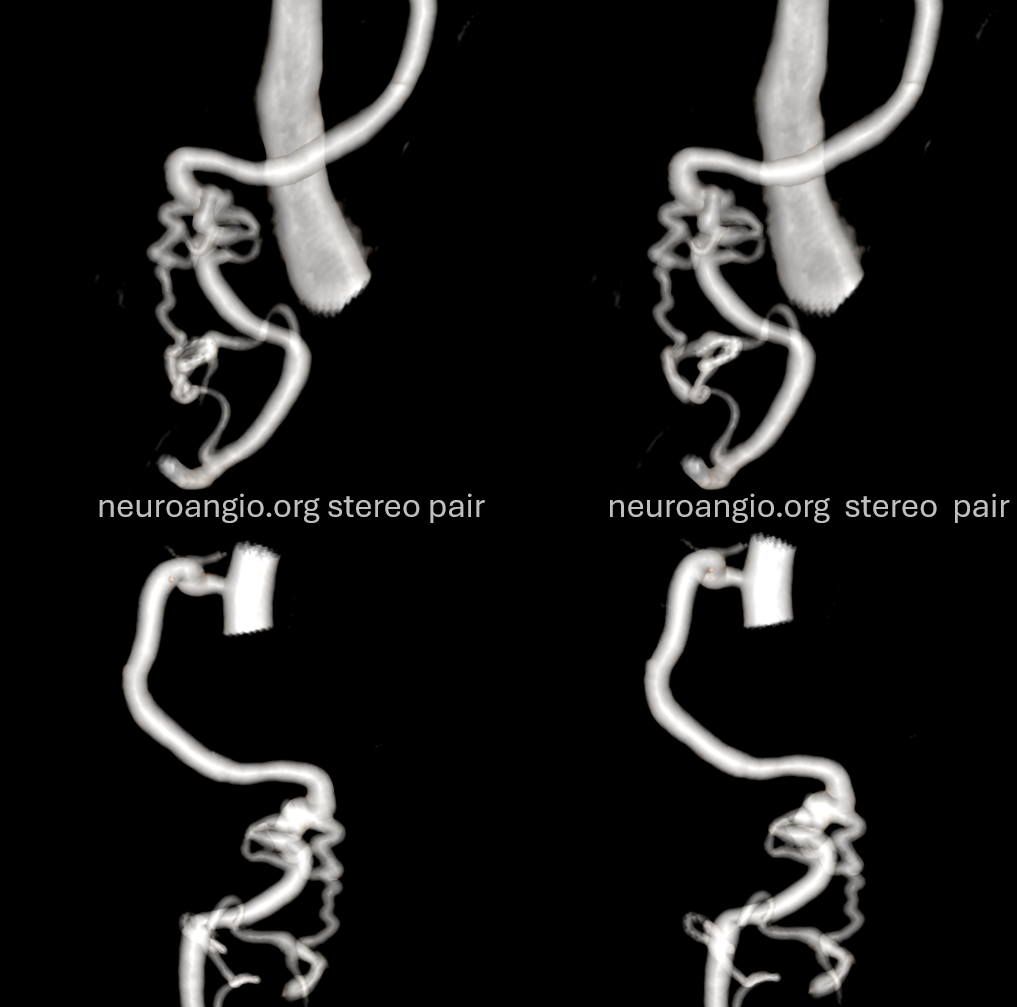

The indispensible STEREO pair

Lateral spinal artery is a pathway by which PICA can be reconstituted in cases of more proximal vertebral occlusion — again recognizing that PICA is a lateral spinal artery homolog — in effect an enlarged lateral spinal artery capturing territory of the cerebellum in addition to the lateral medulla.  In this patient, the right vertebral artery is occluded just below the foramen magnum due to dissection.  The C1 radiculopial artery (purple) connection to the lateral spinal artery (red) allows for reconstitution of the vermian branch of the PICA (black).  The lateral spinal artery inferior to the C1 radiculopial artery is marked with a pink arrow.  Notice also presence of the anterior spinal artery (yellow) perfectly contrasting its anterior and medial position to that of the spinal artery.  The C1 radicular branch (purple) is in effect the radiculopial artery is acting as a radiculopial artery, homologous to radiculopial supply of the posterior spinal arteries at the thoracic and lumbar levels (see Spinal Arterial Anatomy) The C1 muscular branch (green) opacifies the occipital artery (white) and deep cervical artery (blue).